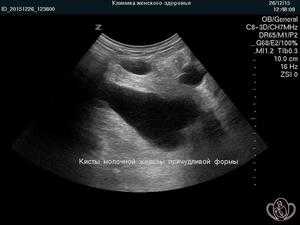

- УЗИ молочной железы. Позволяет определить наличие ответвлений и распознать многокамерное образование, а также отличить кисту от фиброаденомы (уплотнение из железистой ткани без жидкости внутри).

Уплотнение молочной железы может образоваться в любой части этого органа, но чаще обнаруживается в области над соском. Киста в левой груди диагностируется чаще, чем образование с правой стороны. При кисте молочной железы симптомы заболевания зависят в первую очередь от размеров и степени запущенности патологии на данный период. Мелкие (до 0,5 см) кисточки в молочных железах могут никак не проявлять себя и обнаруживаются только при ультразвуковом исследования или на маммографических снимках. Крупные образования — свыше 1,5 см — легко прощупываются под кожей.

При первом обращении врач физически осмотрит грудь и путем пальпации определит наличие уплотнений. Для уточнения диагноза обычно дополнительно доктор назначает УЗИ молочных желез, которое покажет заполнена ли опухоль в груди жидким содержимым или она твердая. Жидкое содержимое обычно подтверждает наличие кисты грудной железы, затвердения указывают на фиброаденому либо злокачественное новообразование.

Основными методами диагностики служат пальпация, которую проводит маммолог при осмотре, УЗИ и маммография, а также МРТ. Даже при пальпации врач уже может определить наличие кисты средних размеров. УЗИ и маммография позволяют найти кисты мелких размеров, а также определить наличие внутреннего кистозного образования, определить форму, размер и точное количество. При обнаружении папиллом берут биопсию для исследования на раковые клетки.